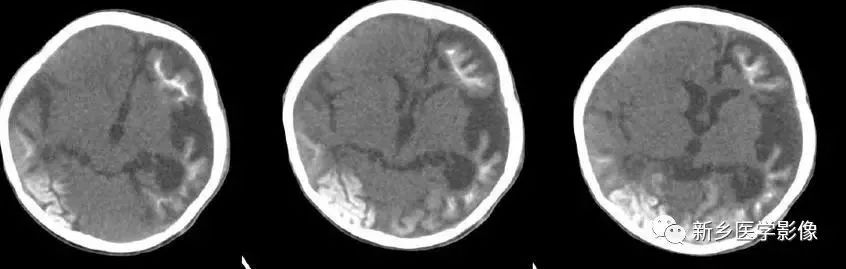

CT和MR均能够很好显示无脑回和巨脑回畸,表现为大脑半球表面几乎呈光滑状,仅可见少数宽阔、粗大、平坦的脑回,脑沟缺如.脑灰质增厚,脑白质变薄,灰白质分界面异常平滑,见不到白质向灰质内伸入的现象。常见透明中隔腔存在.侧脑室扩大,蛛网膜下腔增宽。

(3)无脑回和巨脑回

无脑回和巨脑回是一组因神经元移行异常所致的脑回发育异常。巨脑回也称平滑脑。巨脑回指有部分脑回存在,这些脑回异常增大增宽.脑沟变浅。巨脑回主要位于额、颞部。无脑回上要位于顶、枕部。

临床上,无脑回和巨脑回畸形患儿均表现有小头畸形和轻微的面部异常,完全无脑回畸形常在两岁前死亡.不完全无脑回畸形存活常能长期。